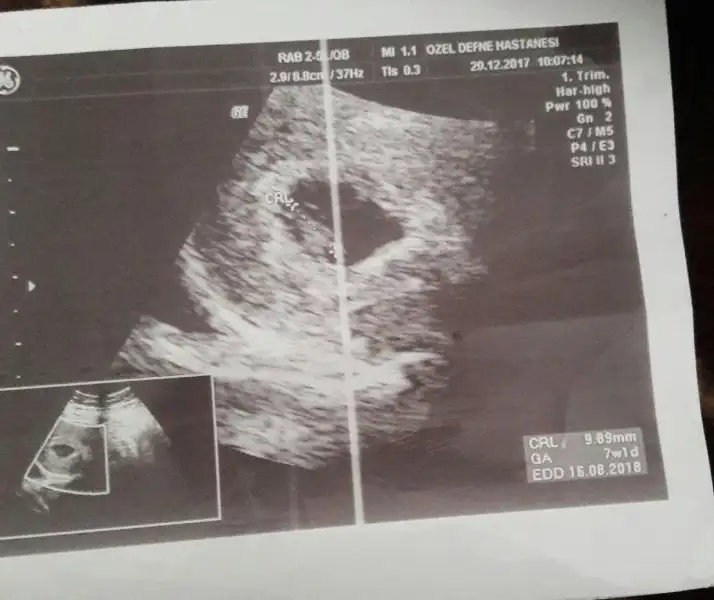

Yenı uyeyım :) 6 haftalık ultrason goruntumuz sızce cınsıyetı ne olabılır?

Eki Görüntüle 2088195 Eki Görüntüle 2088194